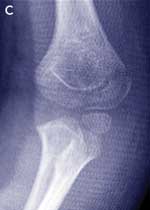

Case study — a 4-year-old girl with a painful left elbow after a fall

The parents of a 4-year-old girl bring their daughter to you after she has fallen about 1 metre from climbing equipment onto her outstretched arm. The girl is complaining of pain in her left elbow. She is unable to straighten her arm without pain and can only flex to 110°. The elbow looks swollen, mainly on the medial aspect. She has diffuse tenderness around the elbow and is unable to supinate or pronate her arm. There is no neurovascular compromise. Management

Lateral condyle fractures are inherently unstable and take a longer time to heal than supracondylar fractures. They should be managed by internal fixation in most cases. This case illustrates that it may be difficult to diagnose these fractures and that close follow-up is needed to prevent complications. |